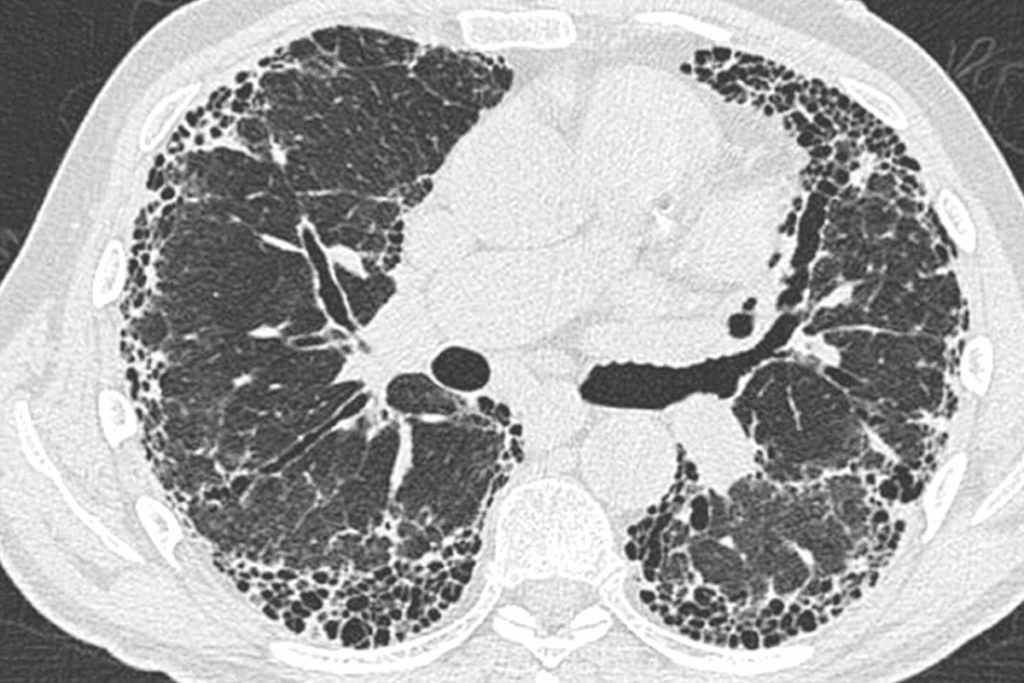

A CT scan lung biopsy removes lung tissue or growths. It helps diagnose lung conditions like cancer, tuberculosis, and interstitial lung disease. The main goal is to get a tissue sample for pathological examination.

Recent studies show CT scan lung biopsy can detect malignancy up to 90 percent of the time. This makes it a very effective tool for diagnosing lung cancer and other conditions.

The diagnostic yield of a CT-guided lung biopsy is its ability to give a clear diagnosis. It’s very good at getting tissue samples from lung nodules and masses. This makes it accurate for diagnosing lung conditions, including cancer.

Research shows that CT biopsy lung procedures often get the right tissue samples. The CT’s precision helps target lung nodules, even small or hard-to-reach ones. This is key for treatment planning and better patient results.

Though rare, serious complications can happen. One big risk is pneumothorax, or a collapsed lung. This occurs when air leaks into the space between the lung and chest wall.